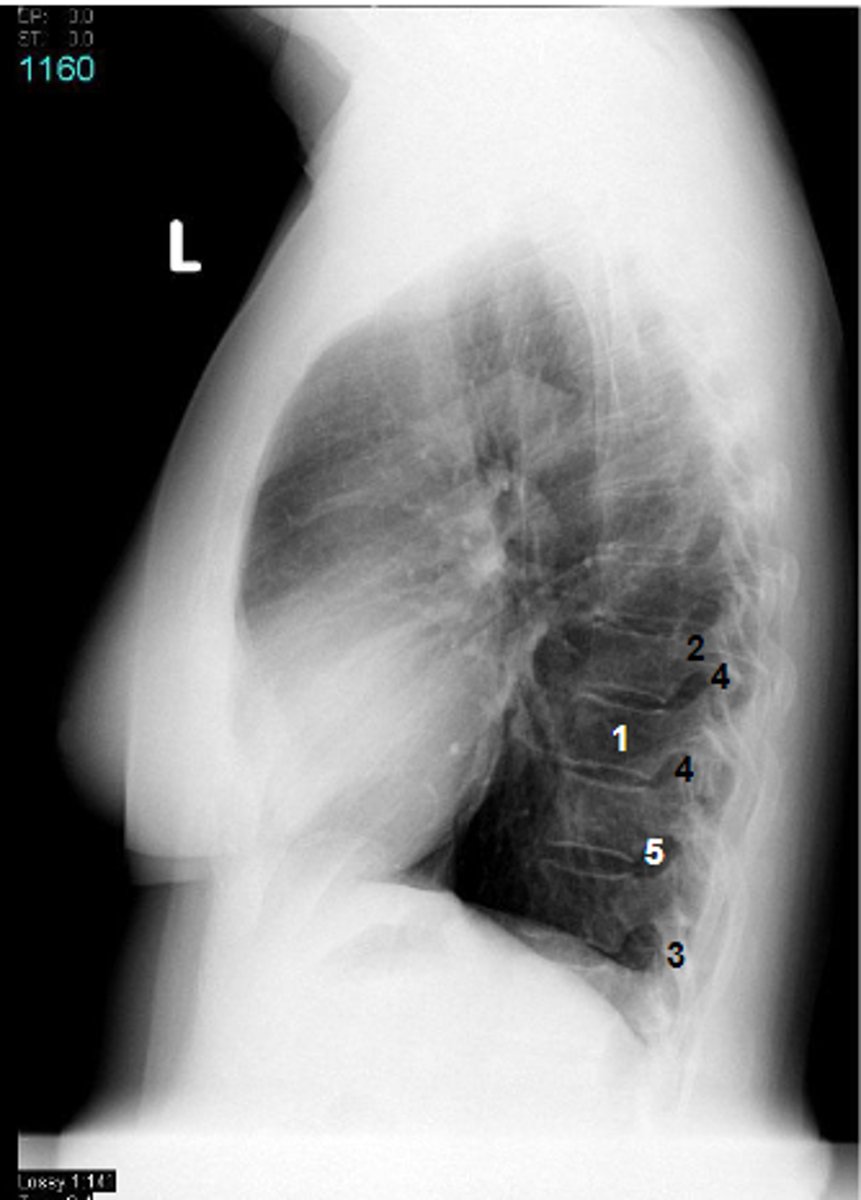

1

at what number is the body

2

at what number is the pedicle

3

at what number is the spinous process

4

at what number is the articular process

5

at what number is the intervertebral foramen